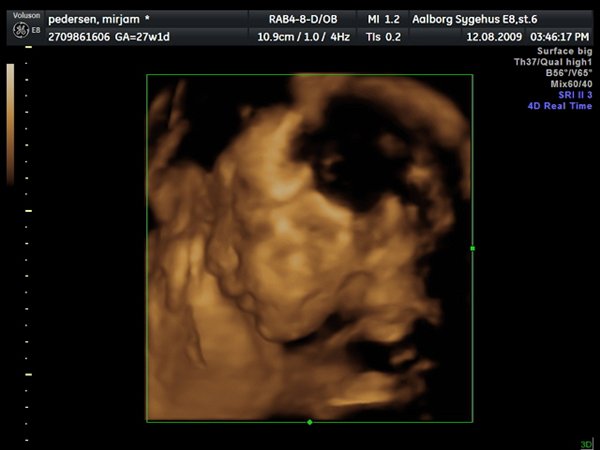

Så var jeg til 3D scanning, og det er en lille PRINSESSE

Hun var bestemt ikke samarbejds villig, vi skulle ihvertfald ikke bestemme hvordan hun sku ligge, så hun lå med hænderne oppe foran hovedet og somme tider med benene oppe foran os.. Så jeg fik rabat kom af med 800kr og han scannede mig ca 50 min. Han sagde hun vejede 990 gram

ups fik ikke billeder tilføjet

Vedhæftede fotos (klik for at se i fuld størrelse)